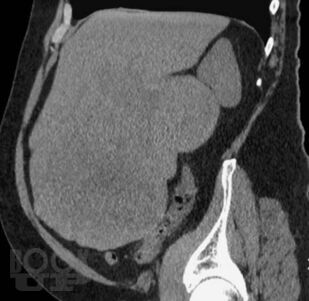

В книге приведены типичные клинико-рентгенологические ситуации, взятые авторами из повседневной практической работы в отделе лучевых методов диагностики и лечения Института хирургии им. А.В. Вишневского. Проанализированный материал охватывает хирургические заболевания органов брюшной полости и забрюшинного пространства вне острых или неотложных состояний. В первой части книги читателю предоставлена максимальная возможность сделать самостоятельное заключение о заболевании после анализа жалоб пациентов, анамнеза заболевания и приведенных изображений рентгеновских и КТ-исследований. Во второй части книги читатель может проверить правильность хода своих рассуждений и собственного заключения. Решение подобных ситуационных задач, несомненно, послужит большим подспорьем как начинающим, так и опытным врачам лучевой диагностики в их практической работе.